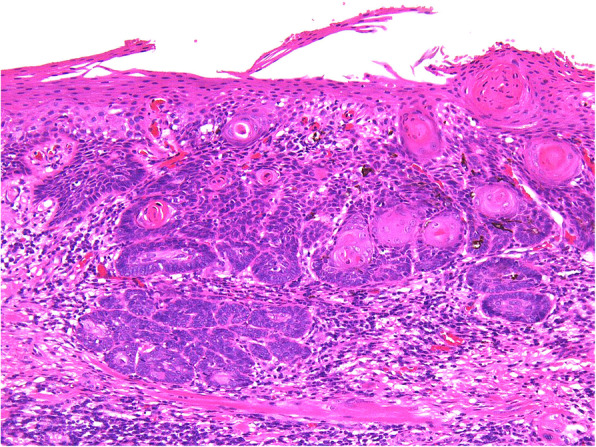

There were false-negative 12 cases in the LBC method. The cytology diagnoses were nine OLSIL cases and three NILM cases, and the histological types were eight SCC cases, two CIS cases, and two severe dysplasia cases. There were six false-negative cases in the conventional method. The cytological diagnoses were five OLSIL cases and one NILM case, and the histological types were five SCC cases and one CIS case (Fig. 1).

Fig. 1.

False-negative representative cases. The deep part of the epithelium reveals downward growth and invasion of tumor cells in the underlying tissue, and surface layer of the epithelium shows keratinocytes without prominent atypia

Despite the improvement in efficacy with the LBC method, there were a certain number of false-positives and false-negatives in this study. There were 12 cases of false-negatives in the LBC method and five cases in the conventional method (false-negative rate; LBC method 18.2%, conventional method 20.7%). When we examined the histology of cases diagnosed as NILM or OLSIL but with SCC, all the histological diagnoses of SCC were found to be well-differentiated SCCs. In addition, all cases were accompanied with well-differentiated keratinocytes lacking strong atypia on the surface. In this study, whether a problem existed with the site of cytology collection cannot be examined. The current diagnostic criteria for the JSCC are limited for the evaluation of atypical superficial keratinocytes. However, even in keratinized epithelium, which is histologically atypical, cytology has the advantage of examining individual cells in detail. Therefore, it might be possible to detect highly differentiated tumor cells that exhibit a tendency to keratinize. The diagnostic criteria of the JSCC take this point into account, but further examination of the diagnostic criteria is probably necessary in the future [8]. Suzuki et al. reported that false-negative cytology was more likely to occur in cases where the exposed cell area for diagnosis was very small or where very limited growth was observed [14]. Because it was difficult to collect basal or parabasal-like atypical cells, cells useful for cytodiagnosis were not sampled, thus leading to false-negative results. Sekine et al. reported [7] a false-negative rate of 22.2%, and our result for oral scraping cytology was acceptable.